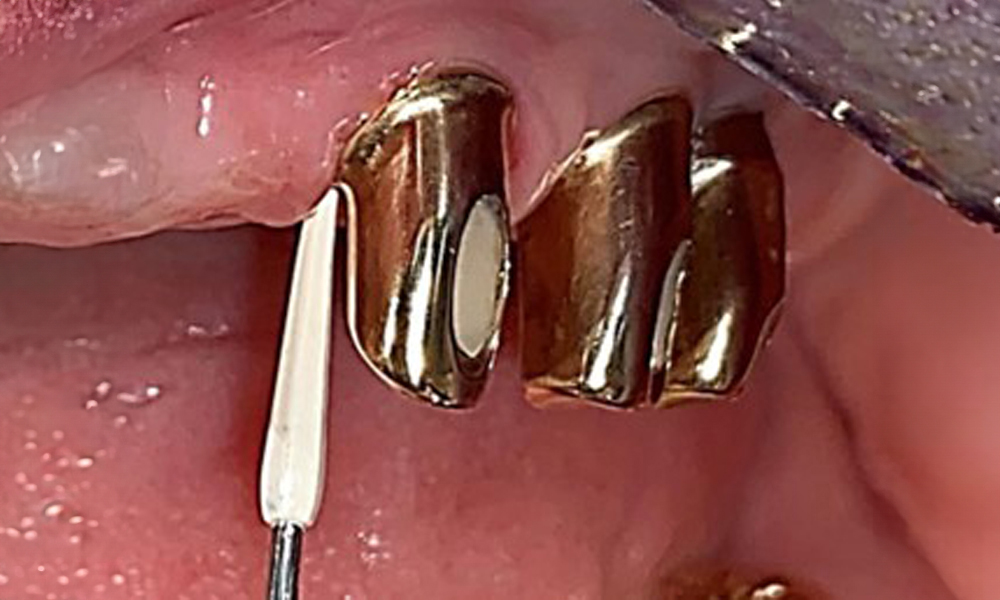

Сондиране на имплант 23 на дълбочина 4 mm с пластмасова сонда, показваща отрицателни резултати от BOP и хиперпластична папила.

Фиг. 6: Сондиране на имплант 23 на дълбочина 4 mm с пластмасова сонда, показваща отрицателни резултати от BOP и хиперпластична папила.

Състоянието на пародонта трябва да се изследва обстойно веднъж годишно. Този преглед осигурява изчерпателна документация за резултатите от пародонталния статус и състоянието на имплантите, включително дълбочината на джобовете, пародонталната рецесия и засягането на фуркациите. Това ще осигури бърза реакция при всяка потенциална прогресия на мукозита, гингивита, пародонтита или периимплантита. Препоръчва се сондиране на импланти с пластмасова сонда. В настоящия случай бе установена мезиална дълбочина на сондиране от 4 mm мезиално от имплант 23. Не бяха открити супурации или кървене, което показва липса на пери-имплантит.

Състоянието на пародонта остава стабилно. Няма възпаление на гингивата или периимплантатните меки тъкани. Дълбочините на сондиране от 1 до 3 mm бяха във физиологичния диапазон. Налице са генерализирани рецесии с размери от 1 до 3 mm. Имплант 23 е с увеличена дълбочина на сондиране от 4 mm, въпреки че няма признаци на секреция или кървене (фиг. 6). Общата стойност на BOP е 12 %.